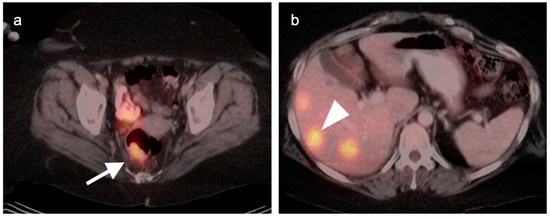

9. Bowel Adenocarcinoma: Colon, Rectum, Small Bowel

10. Anal Carcinoma